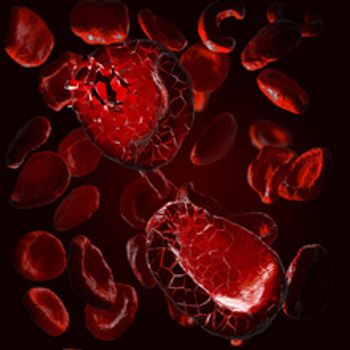

The impacted lot failed a dissolution test, meaning it was taking longer to dissolve once ingested. This can result in less anagrelide available in the body, possibly leading to clotting or bleeding events such as a heart attack or stroke.

The label for Imbruvica now includes information about the possibility of cardiac failure, which has occurred in 1% of patients. Imbruvica is used to treat B-cell blood cancers.

Apokyn and Kynmobi contain apomorphine hydrochloride, which can cause hemolytic anemia that requires hospitalization. The products both treat the loss of muscle movement control caused by Parkinson’s disease.